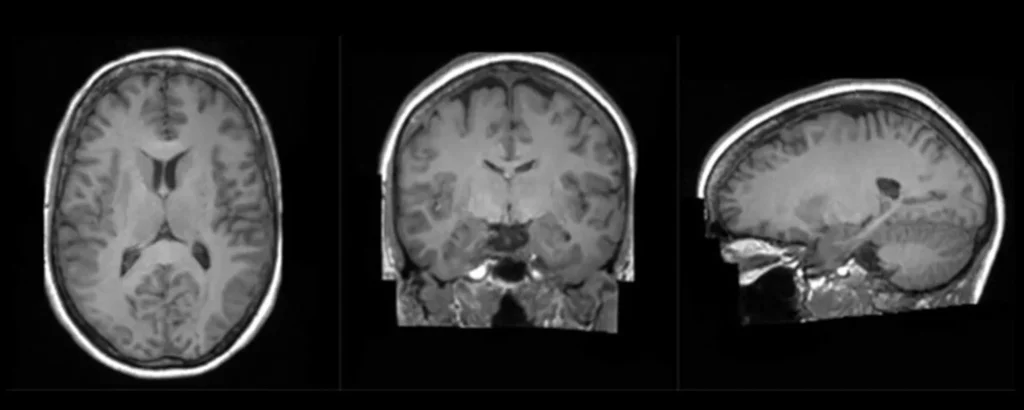

Guest blogger, Craig Rhodes from NVIDIA talks about one of the key programmes, The Synthetic Brain Project, which is benefitting from the computational power of the supercomputer, NVIDIA Cambridge-1 which is housed at Kao Data. Last month, the launch of the NVIDIA supercomputer Cambridge-1 cemented the ultimate collaboration between artificial intelligence (AI) and healthcare, and […]